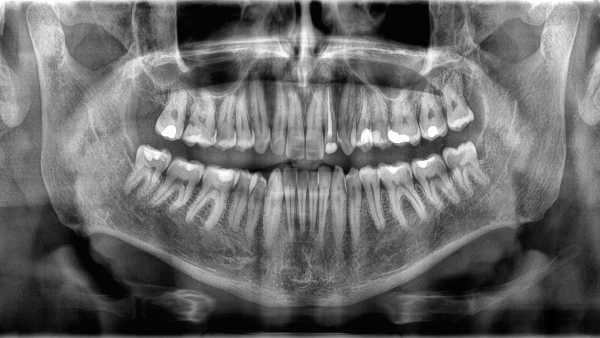

Why don’t teeth count as bones?